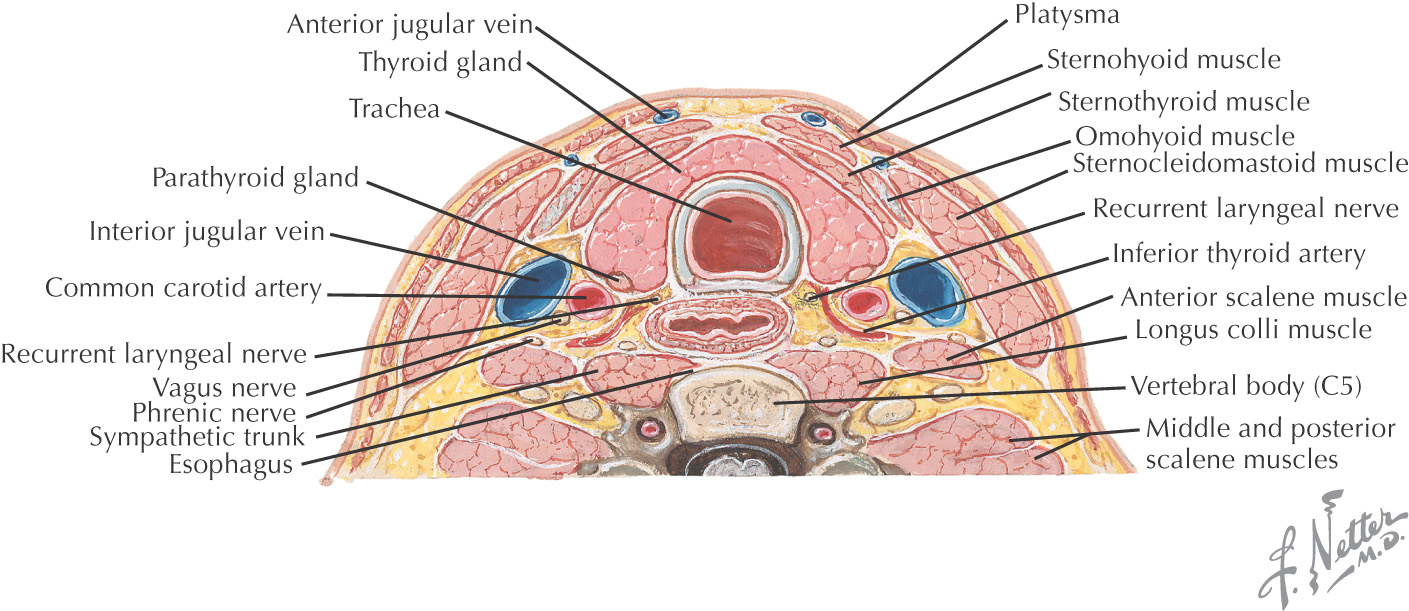

Overview and Topographic Anatomy

Fascia: a band of connective tissue that surrounds structures (such as enveloping muscles), giving rise to potential tissue spaces and pathways that allow infection to spread

In the neck, it is divided into 4 regions:

• 2 neurovascular compartments

Also divided into 4 layers:

• Superficial layer of deep cervical fascia (investing layer of deep cervical fascia)

• Middle layer of deep cervical fascia

• Deep layer of deep cervical fascia

• Carotid sheath (composed by the contribution of all 3 layers of deep cervical fascia)